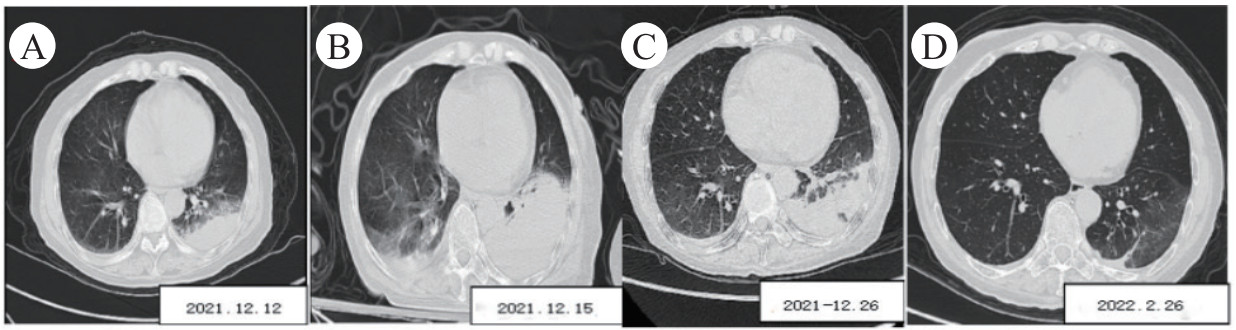

所有患者入院前都进行肺部CT检查。影像中4例重症鹦鹉热肺炎病例均出现肺部实变伴有支气管充气征,均观察到毛玻璃影,其中2例左肺受累、1例右肺受累、1例双肺受累,同时还发现1例伴有纵隔淋巴结/肺门淋巴结肿大,3例伴有少量胸腔积液。

注:A为入院时; B为入院第3天; C为入院第14天; D为入院第72天 图 1 75岁女性重症鹦鹉热肺炎的胸部CT影像(案例3)

本研究中所有的患者都有接触史,其中1例患者接触过鸽子,1例患者饲养家禽,其余2例患者接触过活禽市场。对经mNGS确诊的鹦鹉热衣原体感染患者的回顾性分析显示,4例鹦鹉热衣原体重症肺炎病例都是通过mNGS诊断的。发烧、肌痛和头痛是最常见的症状,这与之前的报道不同[12-13]。实验室数据通常显示外周血白细胞正常或轻微升高,中性粒细胞、降钙素原和C反应蛋白水平较高。与其他衣原体属物种相比,鹦鹉热衣原体更具致病性,并引起更严重的炎症反应[14]。本研究中的胸部CT结果显示,炎症性病变始于肺下叶,同时伴有支气管充气征和实变,与其他研究中报道的模式不同[15]